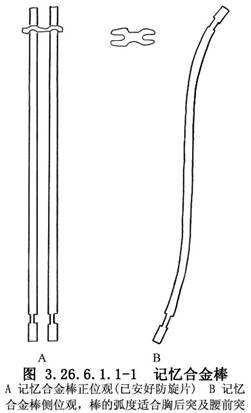

应根据脊柱侧弯超过上下中立位椎体1~2节的长度,选择相应长度的记忆合金棒备用。将备用的记忆合金棒及防旋卡,用无菌巾包裹,高压蒸气灭菌后,外用塑料布包好,置于低温冰箱内备用(图3.26.6.1.1-1)。